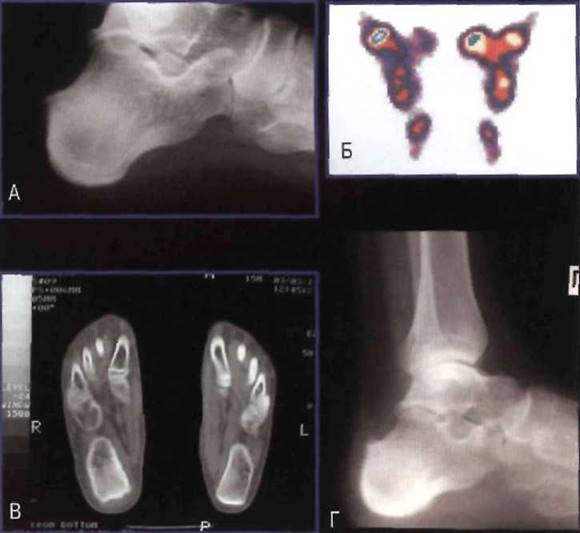

Рис. 23-12. Эрозии пяточной кости у больного ЮАС: А - рентгенограмма; Б - сцинтиграфическое исследование (значительное накопление радиофармпрепарата справа); В - компьютерная томография; Г - прогрессирование рентгенологических изменений с формированием остеофитов верхнего и нижнего краёв пяточной кости при исследовании в динамике через 4 года.